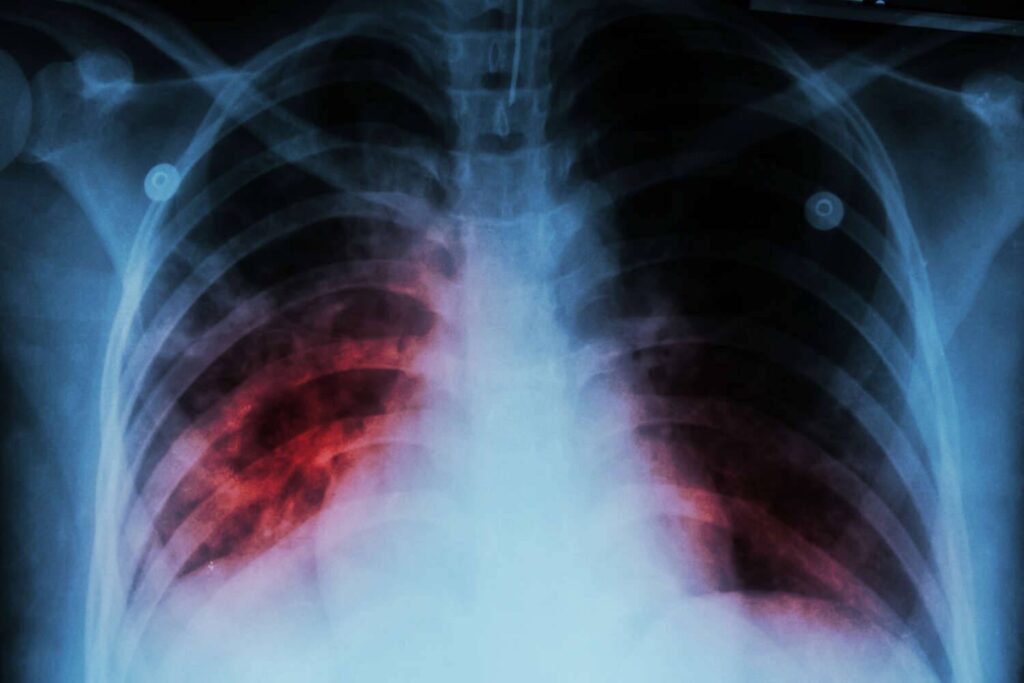

Da der Hauttest falsch positiv ausfallen kann (6), muss der Patient möglicherweise auch einen Bluttest durchführen lassen. Der Bluttest kann die erste Diagnosemethode sein, die bei Personen eingesetzt wird, die gegen BCG geimpft wurden oder gesundheitliche Probleme haben, die das Ergebnis des Hauttests beeinträchtigen könnten. Fällt der Bluttest positiv aus, sind weitere Tests erforderlich, um festzustellen, ob es sich um latente oder aktive Tuberkulose handelt. In diesem Stadium können Röntgenaufnahmen der Brust oder CT-Scans durchgeführt werden.